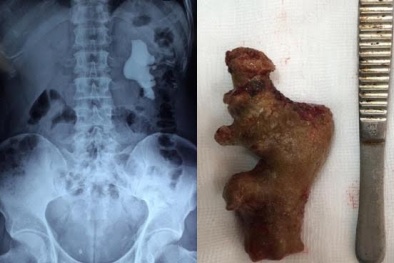

Sỏi thận dài 11cm kích cỡ 'khủng' vì tự ý dùng thuốc nam điều trị

(VietQ.vn) - Bệnh nhân ở Hà Nội phát hiện sỏi thận hơn 10 năm nhưng tự ý dùng thuốc nam điều trị. Kết quả sỏi không giảm mà còn to và dài đến 11 cm.